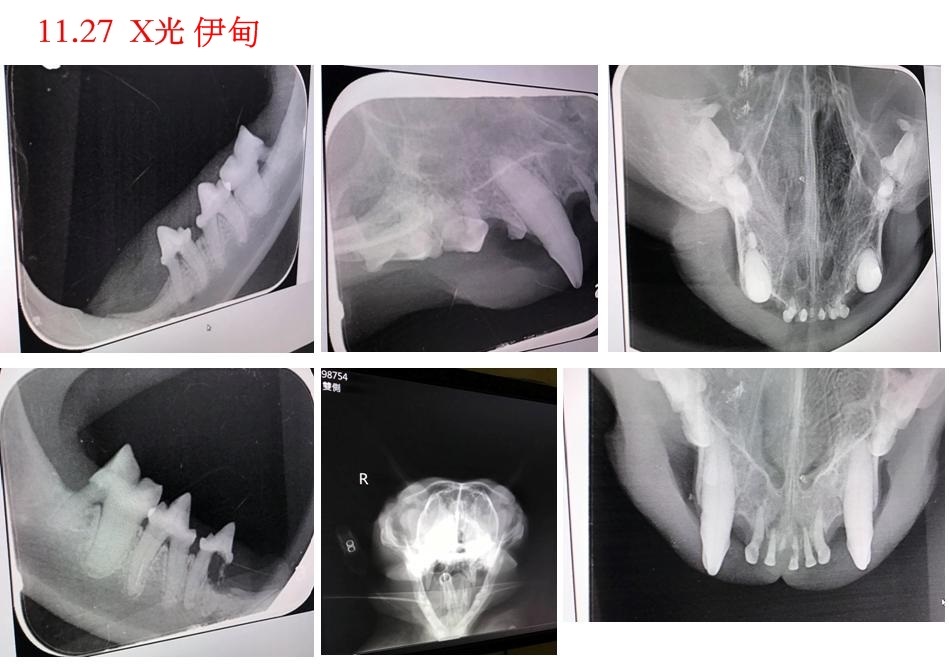

伊甸醫師診斷周全的呼吸較大聲,可能是因為口腔問題引發鼻血,於隔日照齒科X光,並進行牙周手術洗牙拔牙,同時x光發現鼻腔有異物,但不確定是腫塊或者只是分泌物累積,醫師先開藥並建議觀察一個月看鼻腔腫脹是否消失。

將11/27號伊甸的處置過程、X光片、照片、提供給醫師